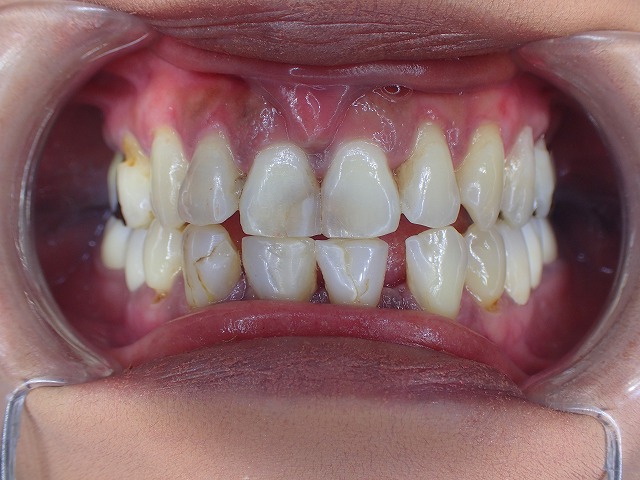

初診時画像 レジン充填 虫歯治療のあとが目立ちます レジン充填は劣化します

レジン充填が多数してあります。

この状態だと劣化して着色以外にも

大きく崩れてくるリスクがあります。

奥歯ないために、前歯で咬む癖があり

歯の先端から崩れ始めています。

下顎の前歯は2本欠損しています。